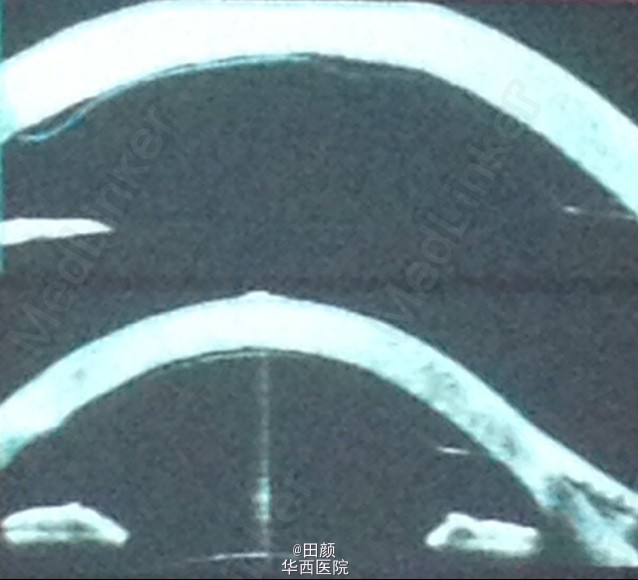

患者男,左眼白内障,行超生乳化术和人工晶体植入术后出现角膜后弹力层脱离。